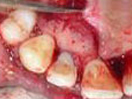

A case of combined REP in one Root and VPT in another Root.

Wound in bone (marked) in one root has healed through REP which is revealed in 6 and 12 months follow up IOPAR, the unaffected pulp in another Root Canal is protected through VPT resulting in the maintenance of validity of Tooth.